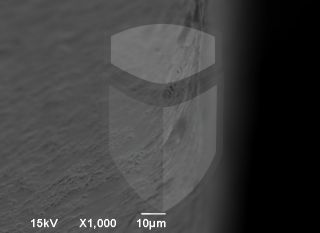

Implante 5 estrelas. Boa usinagem, algumas poucas rebarbas e ótima limpeza.

Topografia/rugosidade:

Marca e tipo de microscópio:

Jeol JSM 6390 Lv